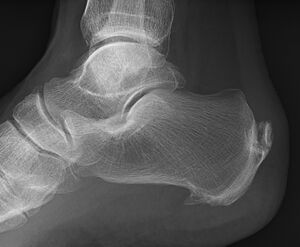

صورة بالأشعة توضح نبتة عظمية على الجوانب الخلفية والسفلية من العقب

المهماز العقبي الخلفي يقع على الجانب الخلفي للعقب وهو استجابة طبيعية لالتهاب اللفافة الأخمصية على مدار الوقت، لكنه يرتبط أيضاً بالتهاب الفقار المقسط (عادة لدى الأطفال). يتطور المهماز العقبي الخلفي على ظهر الكعب عند مدخل وتر أخيل.[3]

المهماز العقبي السفلي هو تكلس في العقب، الذي يقع أعلى اللفافة الأخمصية عند مدخل اللفافة الأخمصية. غالباً ما يكون المهماز العقبي الخلفي كبياً وملموساً من خلال الجلد وقد يحتاج إلى إزالته كجزء من علاج التهاب وتر أخيل.[3]

المهماز العقبي السفلي.

يمكن الكشف عن مهماز العقب بالفحص البدني متبعاً بإجراء الأشعة السينية جانبية للقدم.[بحاجة لمصدر]